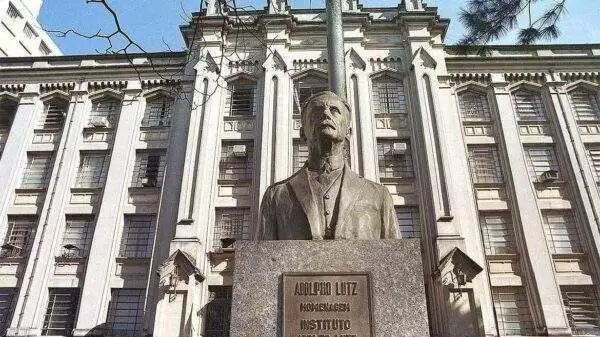

Foi identificado o caso de mais uma variante do novo coronavírus no Brasil. O Instituto Butantan informou que encontrou uma pessoa infectada com a subvariante denominada XE, que mistura duas modalidades da Ômicron.![]()

O caso foi confirmado pelo Ministério da Saúde, que divulgou nota anunciando que recebeu a notificação do Instituto Butantan. A pasta acrescentou que “mantém o constante monitoramento do cenário epidemiológico da covid-19”.

A variante XE é uma combinação de duas cepas diferentes da Ômicron: BA.1 e BA.2. O primeiro caso foi mapeado na cidade de Londres, em janeiro deste ano. Segundo o Instituto Butantan, a taxa de crescimento da XE é 10% superior à da cepa BA.2.

Contudo, o Instituto informa que ainda não há evidências suficientes acerca de mudanças, vantagens e desvantagens da circulação a nova variante em aspectos como gravidade, transmissão e eficácia de vacinas já existentes.